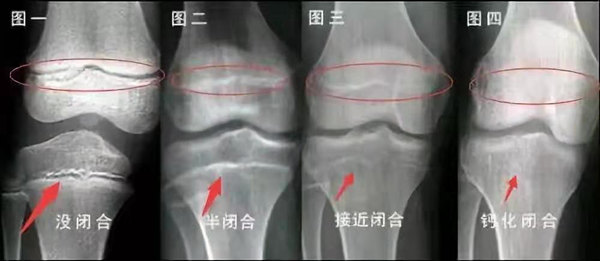

我們都知道,人體的高矮是由骨骼的生長(zhǎng)發(fā)育決定的,特別是下肢長(zhǎng)骨。長(zhǎng)骨呈長(zhǎng)管狀,在長(zhǎng)骨的兩端有一種專(zhuān)管骨骼生長(zhǎng)的骺軟骨,它與干骺端之間有一盤(pán)狀軟骨結(jié)構(gòu)稱(chēng)為骺板(線(xiàn)),在幼兒的X光片上表現(xiàn)為一條較寬的透光帶。 (見(jiàn)下圖)

未成年時(shí)隨著年齡的增加骺軟骨端不斷骨化,骨骼就不斷增長(zhǎng)。當(dāng)骨骺線(xiàn)完全閉合時(shí)骨骼就停止生長(zhǎng),個(gè)子也就不再增長(zhǎng)了。一般骨骺端完全閉合的年齡是18~20歲左右。